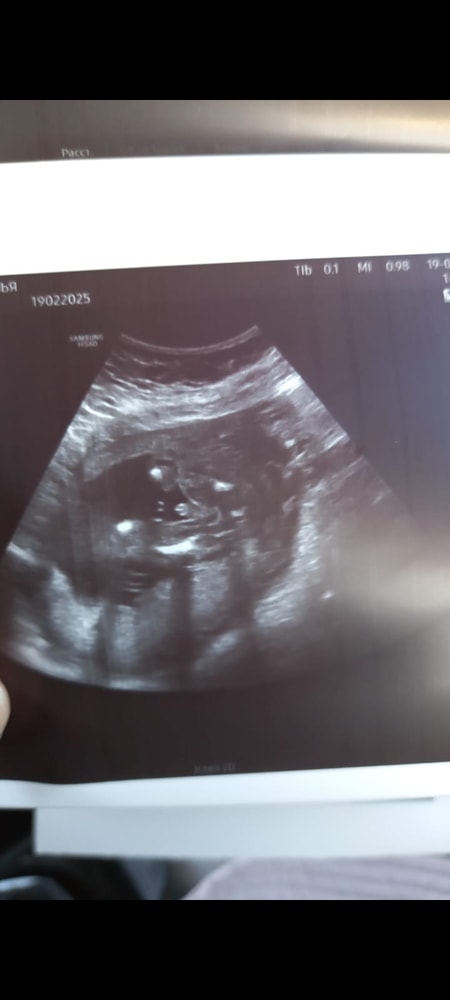

чувствую внутри, что там девочка, я прям уверена была, что дочь. Но вот вчера мне отдали мой конвертик. И я на узи не вижу прям явного «мужичка»)))

прилагаю фото с узи

знаю что у девочек тоже есть бугорок между ножек.

может у кого то были ошибки? Расскажите) как думаете, Надежда есть?))))

Ошибки бывают, особенно если поза плода не позволяла чётко увидеть гениталии - у девочек тоже может быть заметен бугорок. На втором скрининге станет яснее.

Как это не видно? Очень даже видно мужское достоинство,тут не то,что 100% а все 1000000....что паренёк в домике живёт) Тем более вы по узи видели наверняка,как у девочек бутончик выглядит)